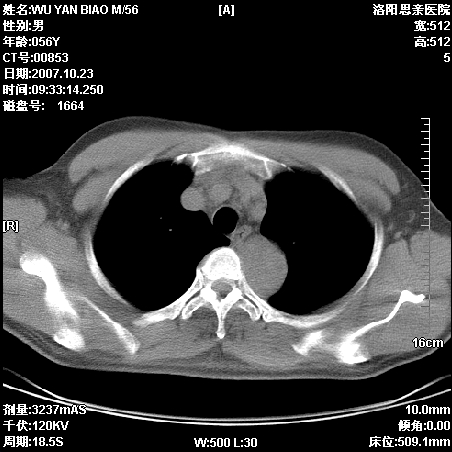

标题: CT10160:M56Y,体检发现,病人无不适,病人随访中 [打印本页]

标题: CT10160:M56Y,体检发现,病人无不适,病人随访中

后上纵隔占位,与肺交界清,宽基底附着脊柱,密度均匀,局部骨质无明确改变.

考虑;神经源性肿瘤,---起源交感n链?,不除外肠源性囊肿.

1、病灶在后纵隔脊柱旁沟内,此处是神经原性肿瘤的好发部位

2、病灶边缘光滑整齐,更说明病灶来于纵隔,由于有胸膜的包裹所以才导致这么光滑的边缘

3、病灶内的密度均匀